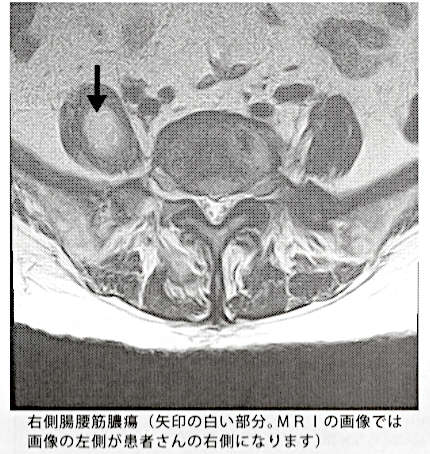

ÉÂ̾¤Ï¡¢£±¡¢¿Õ⳿ձꡡ£²¡¢ÀÔÄDZꡡ£³¡¢Ä²¹ø¶ÚÇ¿¼ð¡¡¤È¤Î¤³¤È¤Ç¤·¤¿¡£

¼õ¿ÇƱ¹Ô¤·¤¿ºÝ¤Ë£Í£Ò£É¤Î²èÁü¤ò¸«¤ë¤È¡¢º¸¿Õⳤè¤êÇ¿¼ð¡Ê¥¦¥ß¡Ë¤¬ÀÔÄÇ¡ÁIJ¹ø¶Ú¡Á±¦¸Ô´ØÀá¤Þ¤Ç³È¤¬¤Ã¤Æ¤¤¤Þ¤·¤¿¡Ê¼Ì¿¿¤ò¥¯¥ê¥Ã¥¯¤¹¤ë¤È³ÈÂ礷¤Þ¤¹¡Ë¡£